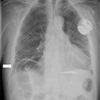

75

Dx

Neumotorax

76

77